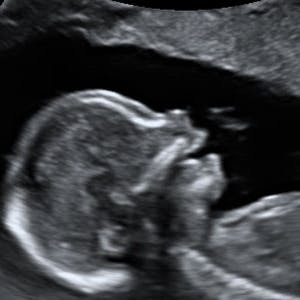

Gravid

Vi gør en dyd ud af at klæde dig godt på både før, under og efter din graviditet. Vi ved, at der kan komme mange spørgsmål til din graviditet, fødsel, amning, din babys udvikling og mange flere emner, derfor har vi samlet guides, tips & tricks samt læsernes egne fortællinger i dette gravid univers.